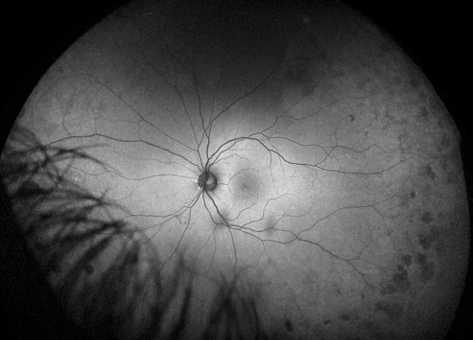

Figure 1. Ultra-widefield color image illustrating predominantly peripheral lesions in a patient with proliferative DR.

Results from a prospective 4-year study conducted by researchers at the Joslin Diabetes Center showed that the presence of predominantly peripheral lesions is predictive of a 3-fold increased risk of DR progression and a nearly 5-fold increased risk of developing proliferative DR.4 Slightly more than half (51%) of the patients who did not have proliferative disease at baseline were observed to have predominantly peripheral diabetic lesions, and 39% had DR progression, a finding that may help identify a subset of patients at higher risk for progression.1 Because these lesions are outside the area of the retina that can be visualized with traditional fundus photography, it is important to use UWF imaging to examine the periphery to accurately assess the severity of DR and evaluate the likelihood of progression (Figure 1).